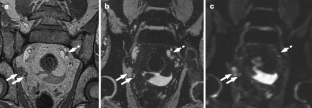

Fig. 1